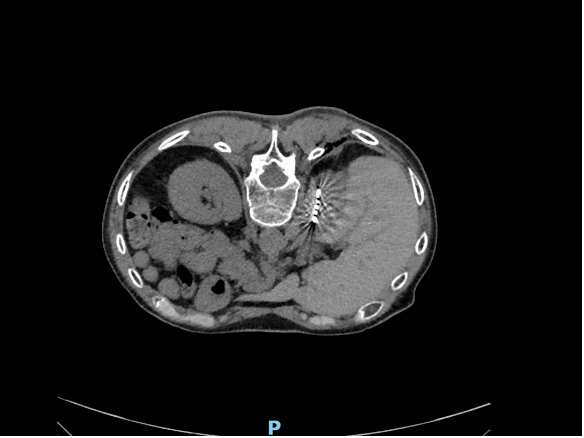

粒子植入治疗前右侧肾上腺病灶(红色标记圈)

粒子植入治疗后右侧肾上腺病灶消失